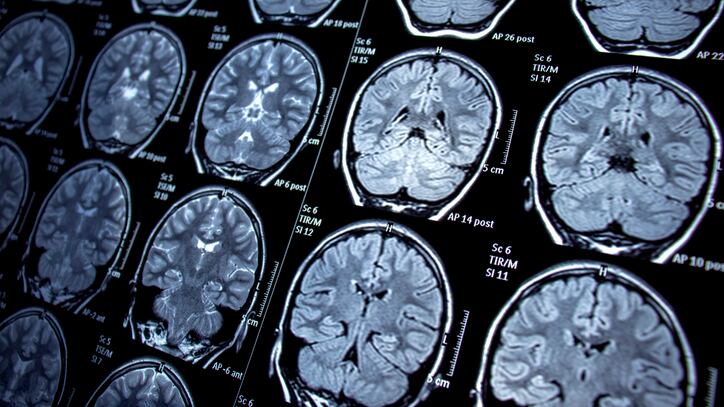

According to The Guardian, the woman developed respiratory symptoms and medical scans revealed issues with her lungs and liver. When neurological symptoms began to develop, the woman underwent an MRI where a mass was seen in her brain.

Doctors began a biopsy of the woman’s brain and when they came to the mass, they saw something wiggle.